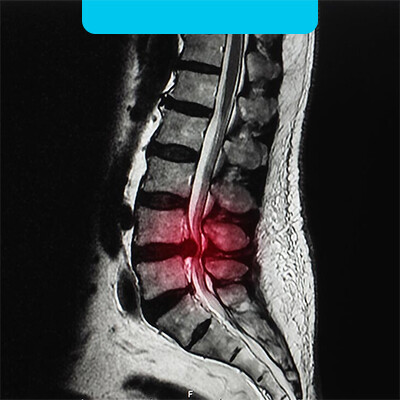

تنگی کانال به معنای اشغال کانال نخاعی توسط دیسک ، لامینا، زائده شوکی میباشد که باعث فشار آوردن به نخاع می شود و این مسئله باعث افزایش درد و در مراحل پیشرفته بی حسی و به مرور در آخرین درجات باعث آتروفی عضلات (لاغری) ، بی اختیاری ادرار و در نهایت فلجی می شود. این تنگی کانال می تونه به دو دسته تقسیم بندی بشه....

سنترال یا مرکزی، لترال یا جانبی.

سنترال : احاطه نخاع و کاودا اکوینا (شبه نخاع) و تحت فشار قرار دادن نخاع توسط دیسک ها ، لامینا ، لیگامان یا رباط های طولی و ....

لترال: این نوع تنگی کانال ناشی از فشار یک طرفه به نخاع می باشد که البته میتونه دلایل یکسانی داشته باشه و فقط نوع فشار به نخاع مهمه در لترال و معمولا سنترال خطرناک تره چون باعث فشار بیشتر و گاها قطعی نخاع می شود.